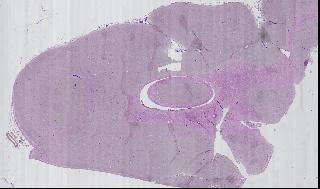

Figure 3. Overview of Slide

There are currently two interfaces to the physical “scanner”: one for grabbing an overview (see Figure 3) of the entire slide, at 25 bits per inch (i.e., the microscope's objective is moved 1mm at a time, and the average color at that point is saved), and another for grabbing a specified region on the slide. In the second case, because of the low speed of directory listings (ls takes quite a bit of time if there are 2000 files), a directory is created for every column scanned. Figure 4 shows the interface used to scan in a rectangular region. The user can use the cursor keys to move the slide, and then select the boundaries.

Using this tool, we can zoom out to view the entire slide, zoom in on a specific region of a single sample, then view a specific field of vision. Figure 5 is a mosaic of one portion of one slide.